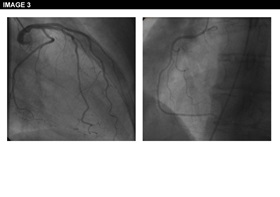

Physical examination is unremarkable. The resting ECG is normal with no ischaemic features (Image 1). She was referred for an ECG exercise stress test. She exercised for 6 min 35 seconds (Bruce protocol), achieved 131% of her heart rate and developed chest pain and breathlessness at peak exercise. Ischemic ST changes were noted which resolved slowly during recovery (Image 2). The patient was referred for cardiac catheterization which showed smooth unobstructed coronary arteries (Image 3). Provocation testing with acetylcholine was performed during angiography when incremental doses of acetylcholine 2mcg, 40mcg, 100mcg were injected in the left coronary system. This resulted in the reproduction of her symptoms, ST depression on the ECG and >75% diffuse epicardial coronary artery spasm of the left coronary artery (Image 4). The diameter of the coronary arteries returned to baseline after intracoronary nitrate administration and both the chest pain and the ECG changes subsided rapidly. Given the diffuse involvement of the distal segments of the coronary artery during the acetylcholine infusion, suggesting the presence of microvascular dysfunction, the patient underwent cardiac magnetic resonance perfusion scanning. Following adenosine stress, which reproduced her usual symptoms, the patient developed subendocardial hypoperfusion of the basal-mid inferior wall & adjacent septum & lateral wall with a circumferential pattern suggestive of microvascular angina (Image 5). On late gadolinium enhancement imaging there was no fibrosis or infarct (Image 6).